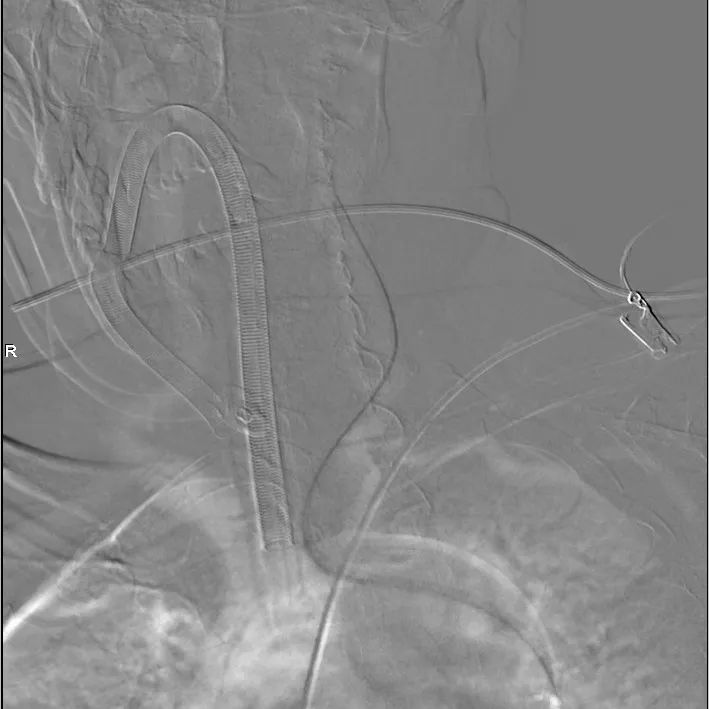

选择合适角度,分别超选支架导管、微导管。

填圈、成篮。

直接释放支架,展开良好,完全覆盖瘤颈。

换至填圈角度,继续填圈。

填塞满意,同时将微导管退出瘤颈,并解脱。

换至释放支架角度,见瘤颈处少许残留,用弹簧圈输送钢丝将微导管再次置入瘤颈,填入弹簧圈2mm/4cm一枚。

术毕,填塞满意。

动脉瘤填塞满意。

支架展开、贴壁良好,分支血管通畅。